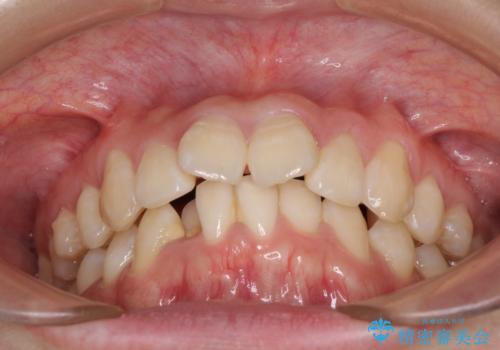

上下前歯の叢生をインビザラインできれいに

- 前歯のデコボコを気にして来院された患者様です。

前歯が重なっていることで口元が閉じにくくなっていたため、歯列全体の側方への拡大と、歯と歯の間を少し削ってスペースを獲得することとしました。